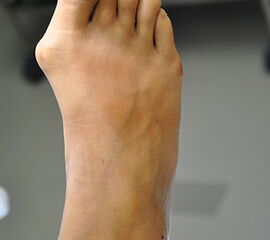

Bei therapierefraktären Beschwerden des Vorfußes und begleitender kontrakter Langzehenfehlstellung, ggf. auch noch zusätzlicher dorsaler Luxationsstellung der Grundglieder, besteht die Indikation einer operativen Korrektur des Vorfußes. Hier steht in der metaphysären Schräg-Osteotomie nach Weil ein etabliertes Verfahren zur Druckentlastung der schmerzhaften Metatarsalia zur Verfügung (Coughlin, 2007; Kitaoka 2002).

Indikation

• Konservativ ausbehandelte Transfermetatarsalgie bei einer Minusvariante des Maestro Vorfußindexes am 1. Strahl.